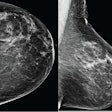

AI interpretation leads to high NPV, recall rates in breast imaging